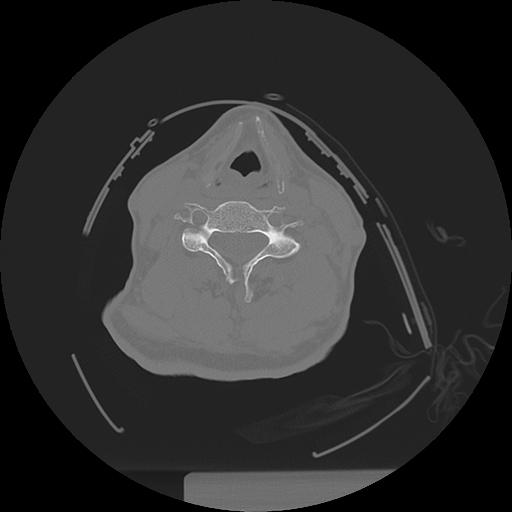

11 HUESO,,Axial,2.0,HUESO,,